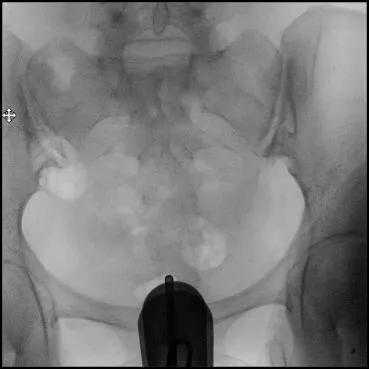

8.透视下注对比剂,动态观察造影剂逐渐膨胀宫腔,流入输卵管,经过伞端流入盆腔的全过程,同时拍摄X光片;

定位片